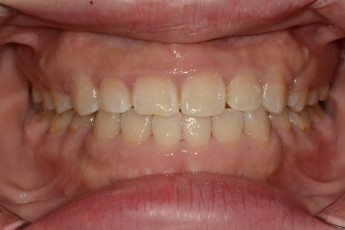

BEFORE & AFTER